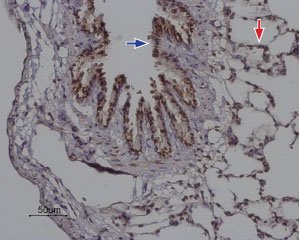

IHC-P analysis of rat lung tissue using GTX54767 ORAI2 antibody. Strong and specific staining is evident in bronchiolar epithelium (blue) and alveoli walls (red). Hematoxilin is used as the counterstain.

Dilution : 1:100